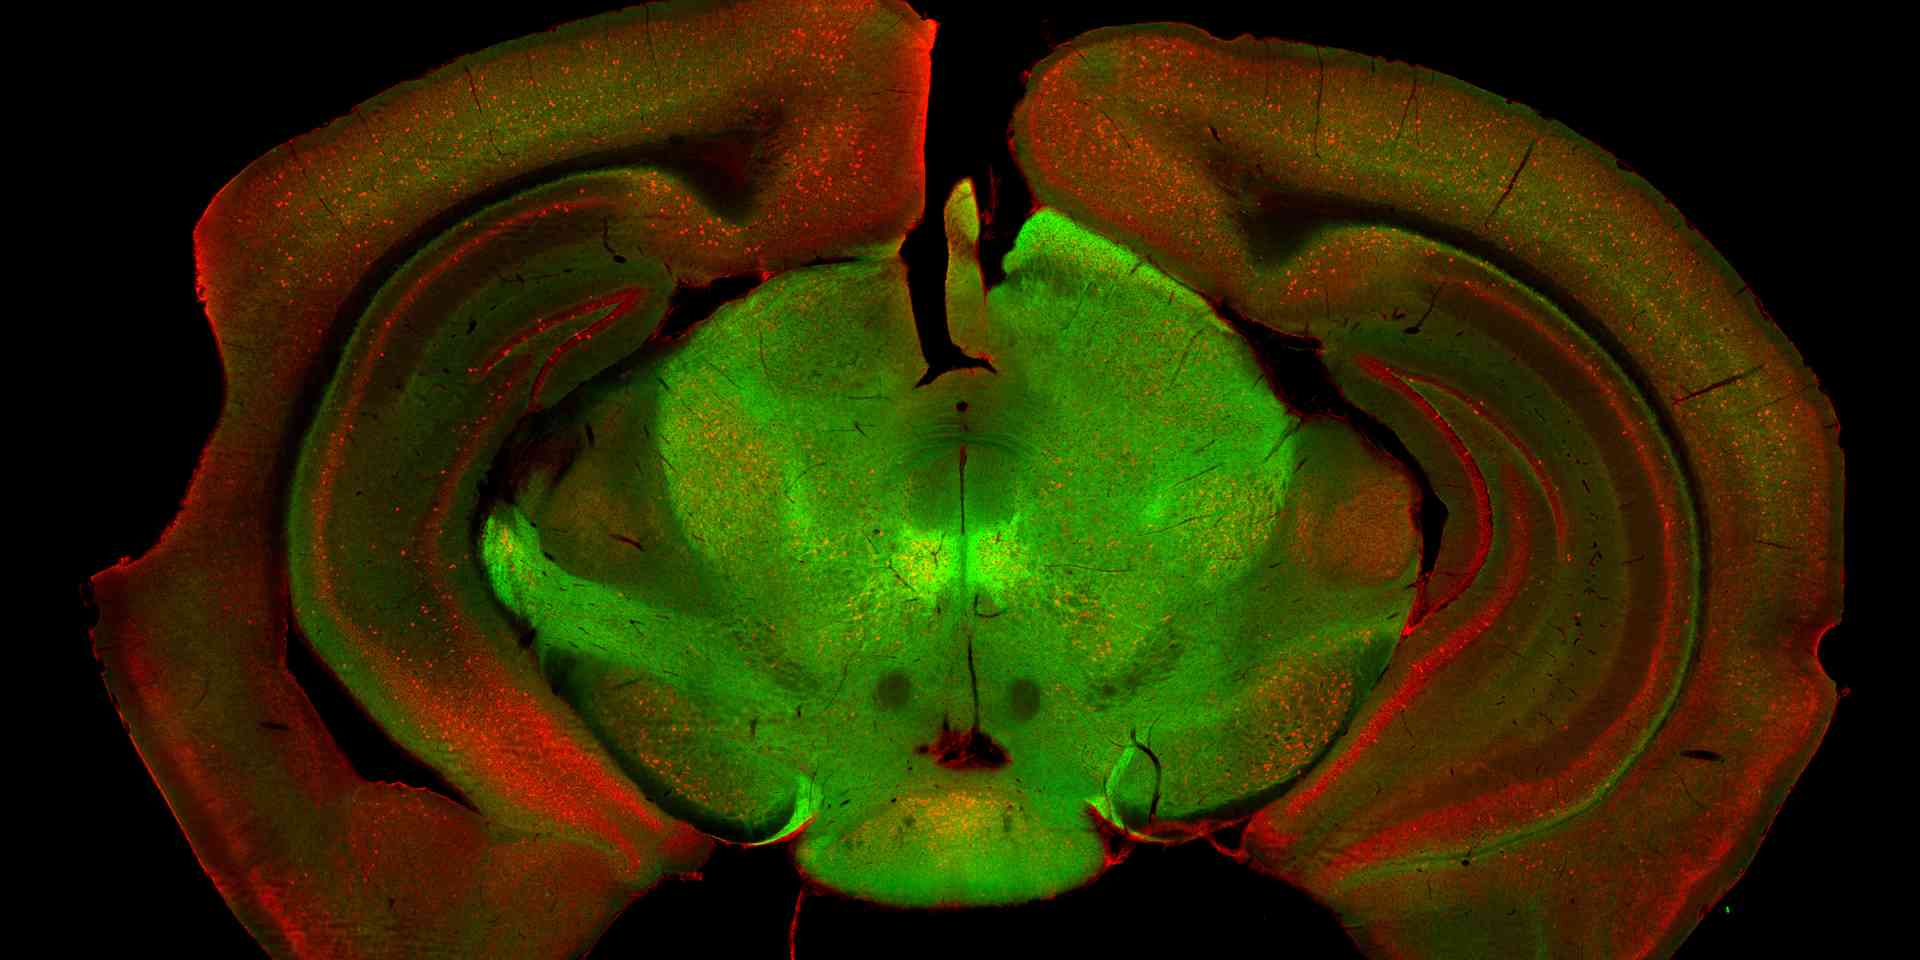

Das Forschungsteam hat dazu die Substantia nigra anatomisch, genetisch und funktionell untersucht. Es zeigte sich, dass diese Region aus mehreren unterschiedlichen Typen von Nervenzellen besteht. Für zwei der Populationen haben die Forscher nun die genaue Funktion aufgeklärt: Während die eine Population für die Ingangsetzung einer gewünschten Bewegung verantwortlich ist, sorgt die zweite für deren Fortführung.

Zwei neuronale Zellpopulationen (grün, rot) in der Substantia nigra, die für die Steuerung der Bewegung verantwortlich sind.